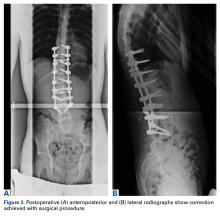

Figure 1.

Preoperative radiographs revealed a 55° right Lenke V C curve (Figures 1, 2). Before the procedure, the patient weighed 111.6 lb and was 175 cm tall. The surgery was uneventful, with a curve correction to about 7° (Figures 3A, 3B). No abnormalities were noted during intraoperative neurologic monitoring. After an unremarkable postoperative course, on postoperative day 19 the patient presented to the emergency department (ED) with abdominal pain, nausea, and vomiting of 3 days’ duration. Right lower quadrant ultrasound revealed nonspecific fluid-filled bowel loops, and the patient was discharged with antiemetics and instructions for hydration.

Figure 2.

Figure 3.